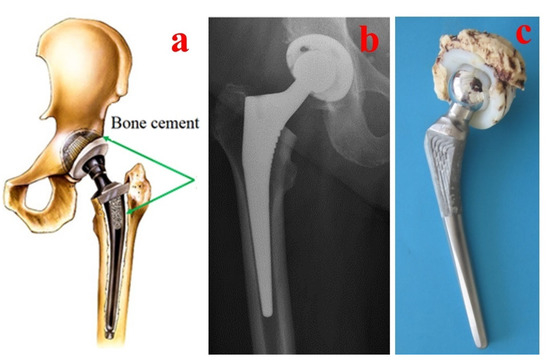

Bone cement performance is directly linked to various parameters such as the mixing method, chemicals used, viscosity, porosity, antibiotics used in the cement composition, sterilization, working temperature, physical and mechanical properties and biocompatibility [61,62]. Additionally, different procedures for intraoperative handling of the bone cements are used in clinical practice. For classical hip arthroplasty, the bone cements are pressured inside the prepared bone and prosthesis components are inserted after into the cement (Figure 3), but in some specific cases such as hip resurfacing prostheses (e.g., Birmingham Hip Resurfacing Prosthesis), the bone cements are pressured inside the femoral head before the insertion of the prosthesis component into the prepared bone (Figure 4).

Figure 3. Aspects regarding the handling of bone cements for classical hip prosthesis fixation: (a) Bone cement application. (b) Postoperative radiography. (c) Failed hip prosthesis.